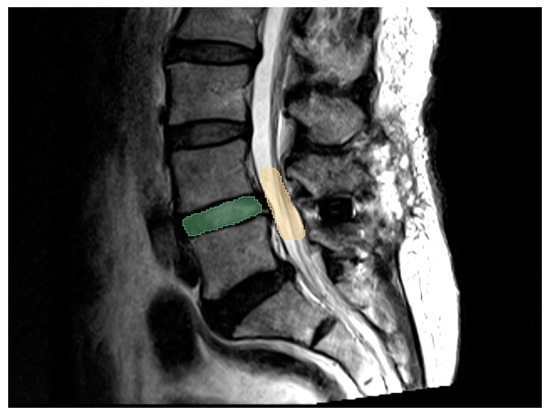

2.4. 3D MRI for Volume Assessmentt

3.3. MRI and 3D Volumetric Outcomes

3.5. Illustrative Case